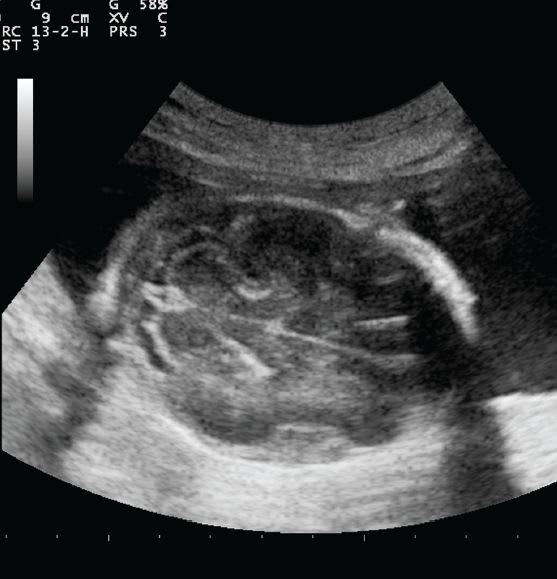

There are more than 200,000 ultrasound machines in use in the U.S. and Europe and about another 100,000 in the rest of the world. The range of applications where medical ultrasound is used includes evaluating symptoms to determine causes of pain or organ damage following illness, examining internal organs, evaluate pregnancies, check blood flow, to determine abnormalities like tumors, and to guide procedures such as needle biopsies.

Intelligent Ultrasound’s 3D Fusion ultrasound products uses a software solution to align overlapping 3D ultrasound scans and provide a composite image reconstruction that affords an increased field-of-view and improved anatomical definition when compared to a conventional 3D ultrasound scan. The images are not simply “stitched” together, but are “warped” to correct for shifts in the point of view from which each scan was obtained and then fused using a novel algorithm. 3D Fusion Ultrasound is particularly useful in applications where a transducer’s field-of-view is insufficient to see a complete object or area of interrogation, and when conventional scans are typically below average diagnostic quality and have insufficient contrast/ detail for confident diagnosis.

A recent clinical study in echocardiography showed that use of 3D Fusion Ultrasound increased the number of scans that could be used for clinical diagnosis from 67.2 percent to 95.7 percent of the total. 3D Fusion Ultrasound almost doubled the number of scans graded as being of good quality compared to single, un-fused scans. These improvements in field of view and quality increase the diagnostic power of 3D Fusion Ultrasound scans, whatever the clinical application.